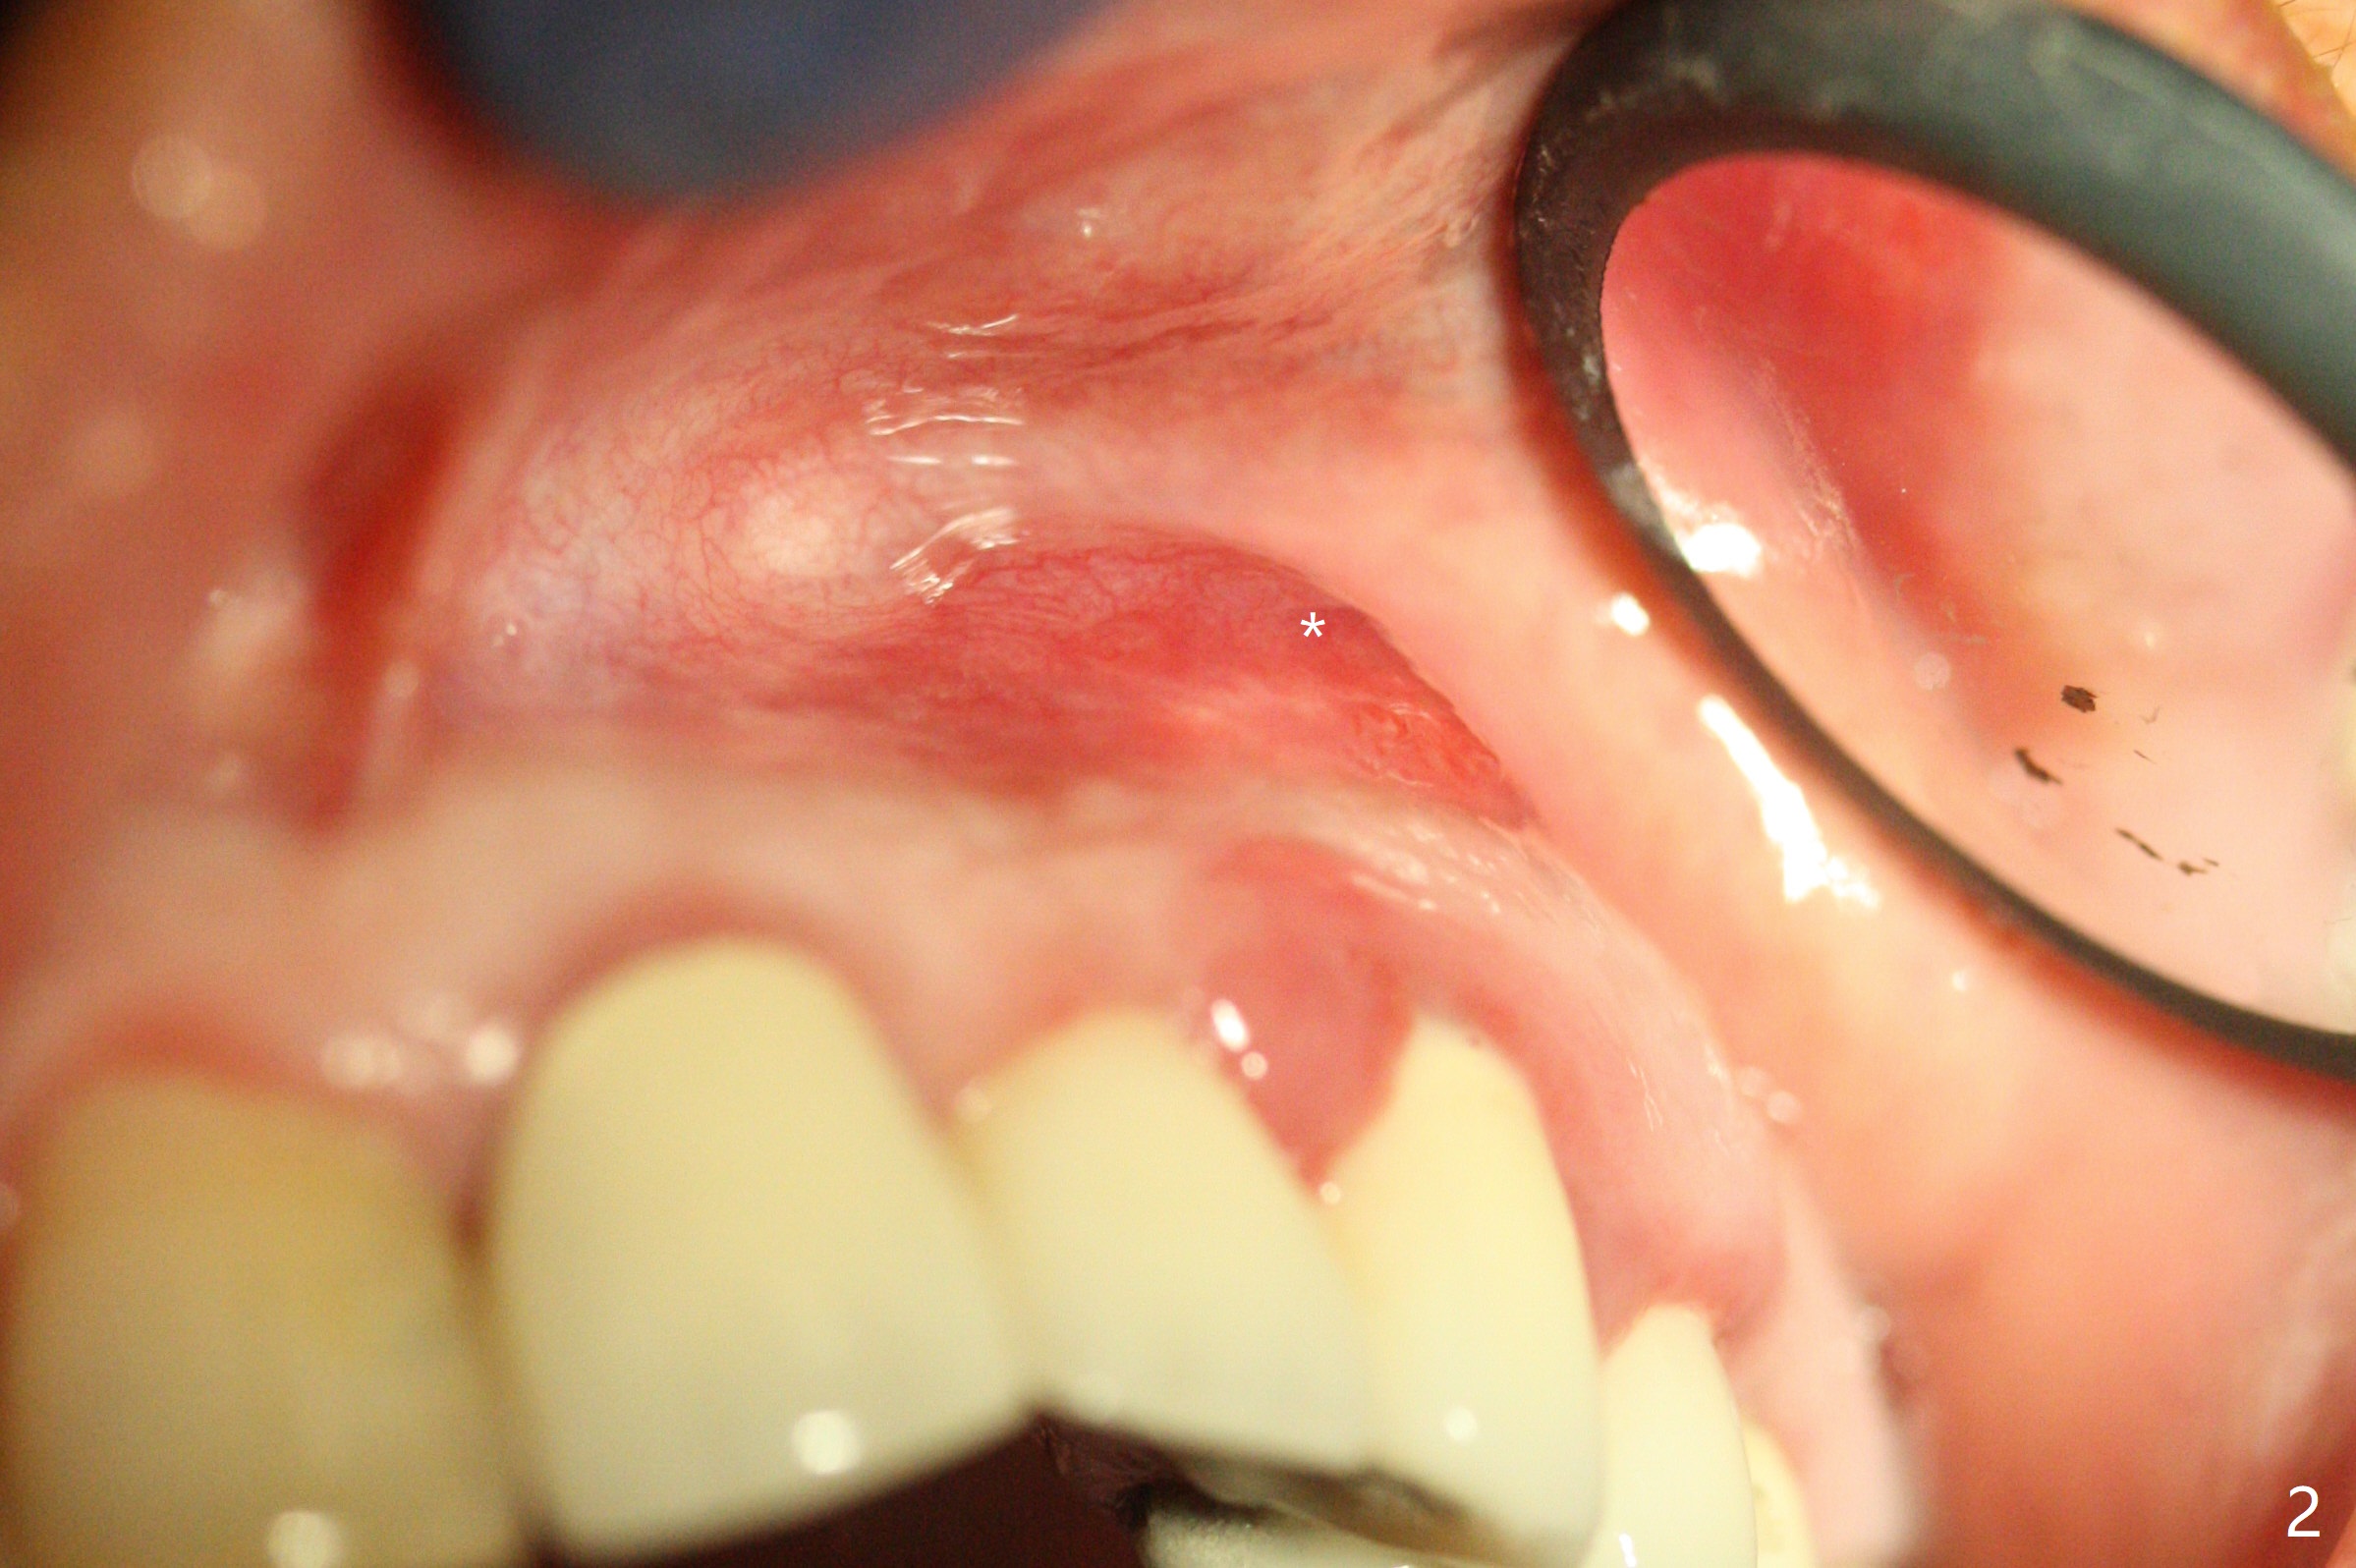

In spite of severe apical infection (Fig1,2 *), a thin narrow strip of the buccal plate (arrowheads, corresponding to the keratinized gingiva) is present when the tooth #11 is extracted. The thin bone keeps the bulging alveolus, i.e., reservoir for bone graft (Vanilla/Osteogen Fig.4 *) after placement of a 3.8x16 mm implant (Fig.3,4). A 4.5x1 mm temporary abutment, placed and trimmed for an immediate provisional, seems to be short in cuff. When an implant is placed deep to prevent periimplantitis, the cuff should be longer, i.e., 3 mm. X-ray should be taken for the depth confirmation after temporary abutment placement. Eight days postop, the mesial gingiva erythema has subsided (Fig.5 < (P: provisional)), while the apical swelling is no longer tender and most likely due to packed bone graft (*). Panoramic X-ray taken 2 weeks postop shows the clearance from the nasal cavity or the maxillary sinus (Fig.6). While the hard tissue around the implant seems to be healthy 5 months postop (Fig.7), the soft tissue is not (Fig.8). The temporary abutment is changed to a cemented one (4.5x5(2) mm) for impression (Fig.8). Since the neighboring crowns are PFM (Fig.6), the new crown will be made of the same material for shade match. Indeed PFM helps shade match in this case as well (Fig.9,10). Switching abutments (from temporary to cemented) makes it difficult to seat the crown. Post cementation X-ray leaves record for future contact loosening. The buccal gingiva remains erythematous associated with open margin (Fig.11 >) 1 year 4 months post cementation. There is no obvious bone loss 1 year 4 months post cementation (Fig.12). It appears that the crown and abutment need to be changed. Although the gingival margin remains erythematous, the gingival hemorrhage is basically lacking due to better oral hygiene during Shelter at Home (1 year 9 months post cementation, Fig.13). Change in abutment and crown will be conducted post coronavirus pandemic. In fact the abutment is incompletely seated (Fig.14 <). In addition, the tooth #12 is symptomatic with PARL associated with the buccal root (*). CBCT indicates possible buccal root fracture (Fig.15,16 ^) and loss of the buccal plate (Fig.16 <).